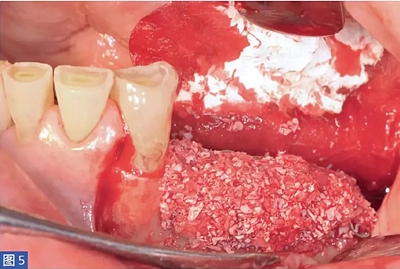

然后用特定的微螺絲固定鈦板。當(dāng)鈦板固定穩(wěn)定后,開始植入骨增量材料。本研究所述的6個病例中,脫蛋白牛骨骨基質(zhì)(DBBM;Bio-Oss,Geistlich)與患者自體骨結(jié)合使用。自體骨與DBBM 的比值約為50:50。骨移植物于口內(nèi)供區(qū)獲得,最好是在下頜骨升支基部區(qū)域。

然后用手磨器械(Hu-Friedy)將收獲的骨塊進行顆?;幚恚⑵渑cDBBM 和患者的靜脈血混合,形成凝膠狀的黏稠度。為了刺激骨的再生,在基骨嵴上鉆出微孔,以開放骨髓腔。然后放置生物材料,填充骨壁和鈦板內(nèi)表面之間的整個空間。

在整個手術(shù)過程中以及術(shù)后12 個月都要評估并發(fā)癥的發(fā)生。在術(shù)后12 個月,患者都要通過視覺模擬量表(VAS)對手術(shù)的滿意度從0(非常不滿意)到10(非常滿意)進行評估。這些問題針對對于治療過程的主觀評價。圖1-12 顯示了兩個典型病例的手術(shù)。

圖5:病例1. 在內(nèi)固定板限定空間中填塞移植物材料。